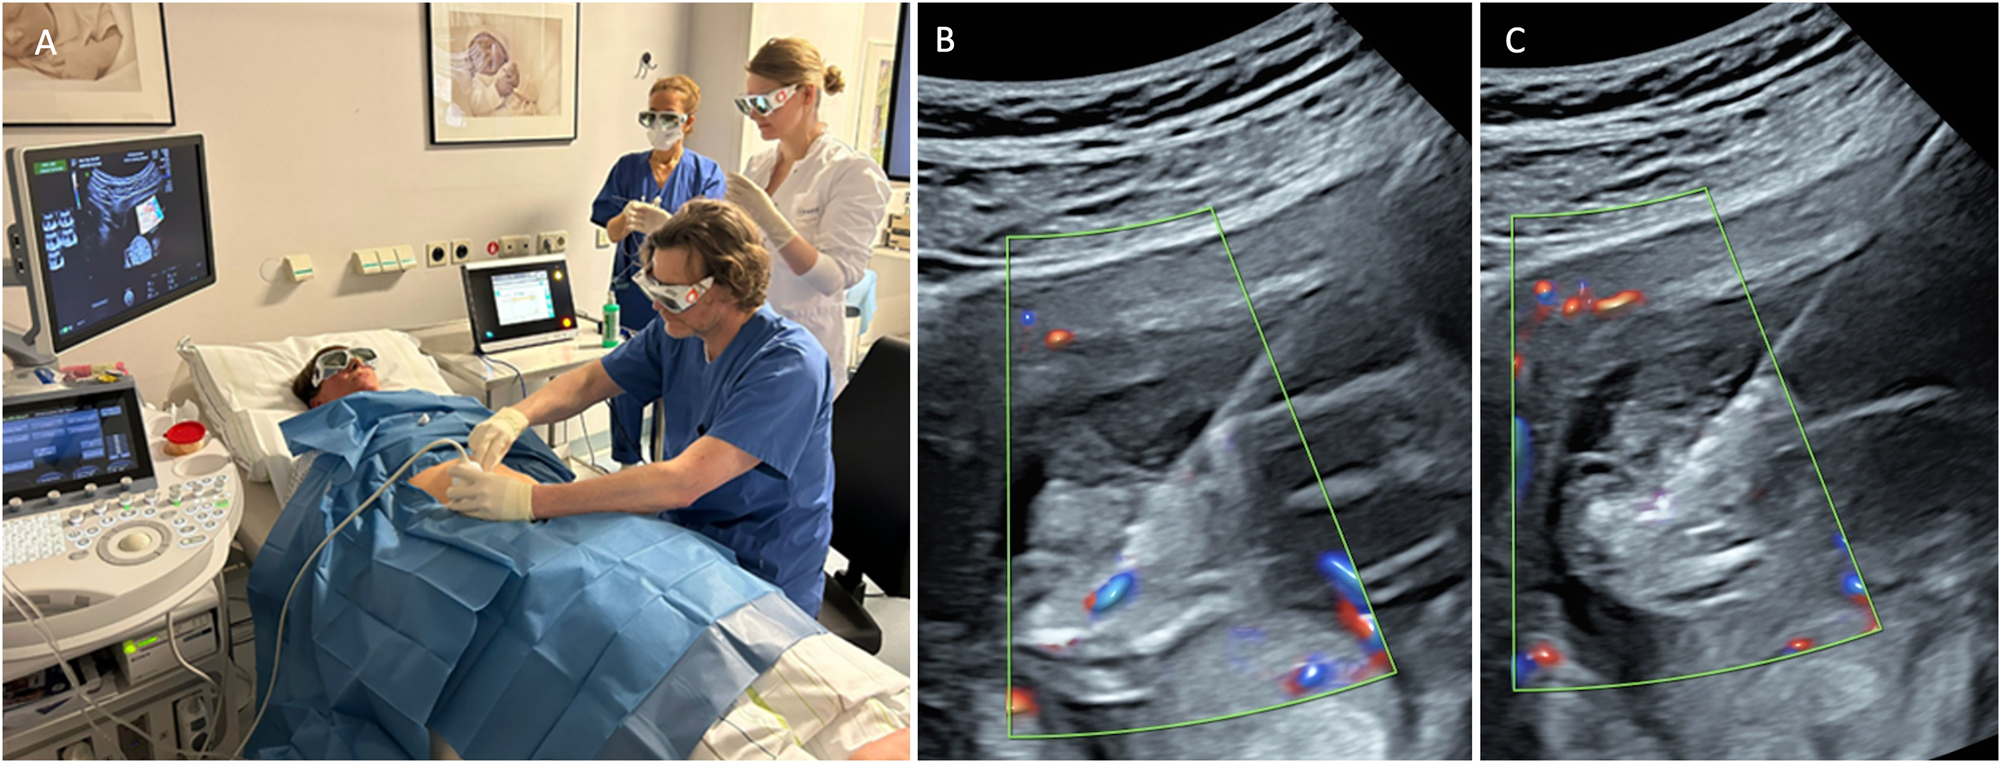

The procedure of intrafetal laser (Figure 8) involves inserting an 18-gauge needle through the maternal abdominal wall into the amniotic cavity under ultrasound guidance, after local anaesthetic has been administered. The needle is positioned directly into the parasitic co-twin at the level of umbilical cord insertion in the pelvic region. A laser fiber is then passed through the needle to coagulate the abnormal blood supply. The thin laser fiber allows precise control of the ablation zone, which is particularly advantageous at earlier gestational ages. The laser energy ablates the blood supply to the acardiac twin, with successful occlusion subsequently confirmed by color Doppler ultrasound [8], 9], 59].

Figure 8:

Intrafetal laser therapy performed in the first trimester (A) procedural setup. (B) Ultrasound-guided insertion of an 18-gauge needle into the parasitic twin at the level of the pelvic region, targeting its vascularization. (C) Laser fiber insertion through the needle for coagulation of the vessel, resulting in complete occlusion.